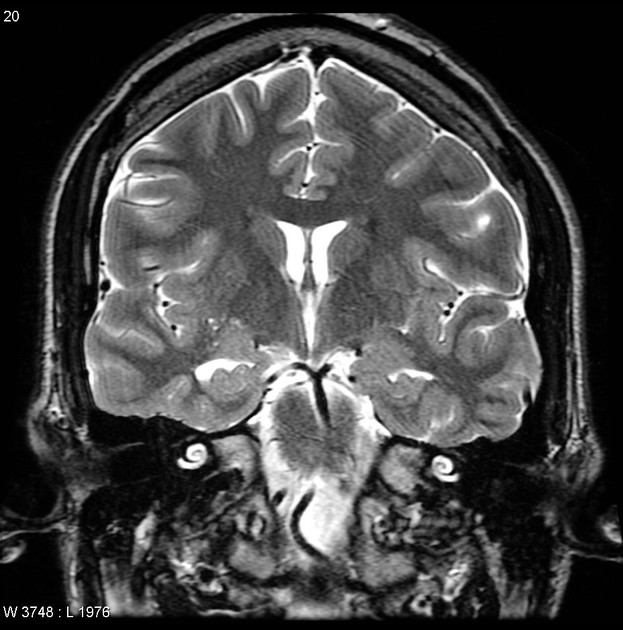

Figure 9.2: Normal brain MRI, coronal view. The two large curved structures in the center are the lateral ventricles, filled with cerebrospinal fluid (appearing bright white on this T2-weighted sequence). The hippocampi are visible as small oval structures just below and lateral to the ventricles on each side.